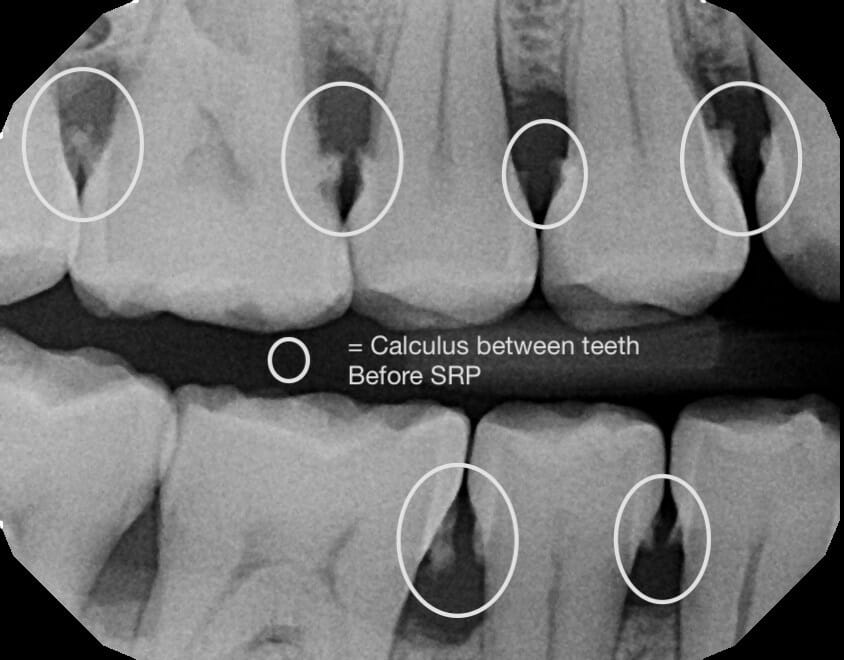

Scaling and Root Planing (SRP), which is commonly referred to as a deep cleaning or gum therapy, is the removal of plaque along with smoothing the roots of your teeth. And when patients who visit our office are diagnosed with gum disease, a deep cleaning is what we’ll recommend.

Some typical signs of gum disease that we most commonly see in the office are swollen and bleeding gums (especially while brushing), calculus near or below your gums, bad breath, and pain in your gums.

However, having one or many of these symptoms doesn’t mean that you can’t dramatically improve your oral health. Depending on the stage and severity of your condition, the deep cleaning you’ll receive at MFD – in combination with improved habits and oral hygiene that we’ll cover – can help you get back on the right path for your gums and teeth.